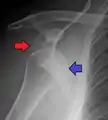

| Anterior dislocation of the left shoulder. | |

An anterior dislocation of the shoulder

Anterior dislocation of the right shoulder. AP X ray